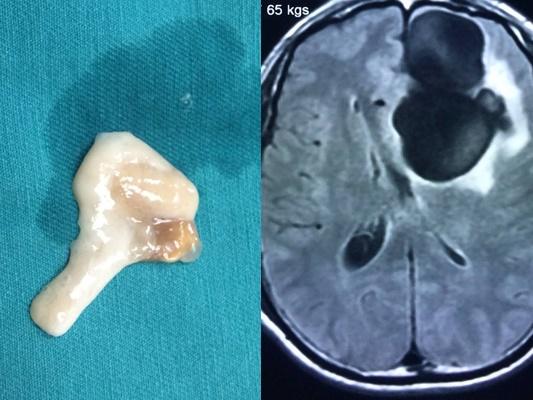

Anh T. được gia đình đưa đến viện trong tình trạng huyết áp tụt, sốc nhiễm khuẩn, viêm cơ tim, suy gan, suy thận và rối loạn đông máu nặng. Các xét nghiệm khẳng định bệnh nhân bị nhiễm liên cầu khuẩn lợn.

Nhờ được chẩn đoán, điều trị sớm, đúng và tích cực, bệnh nhân đã khỏi bệnh và ra viện sau 21 ngày điều trị tại bệnh viện.